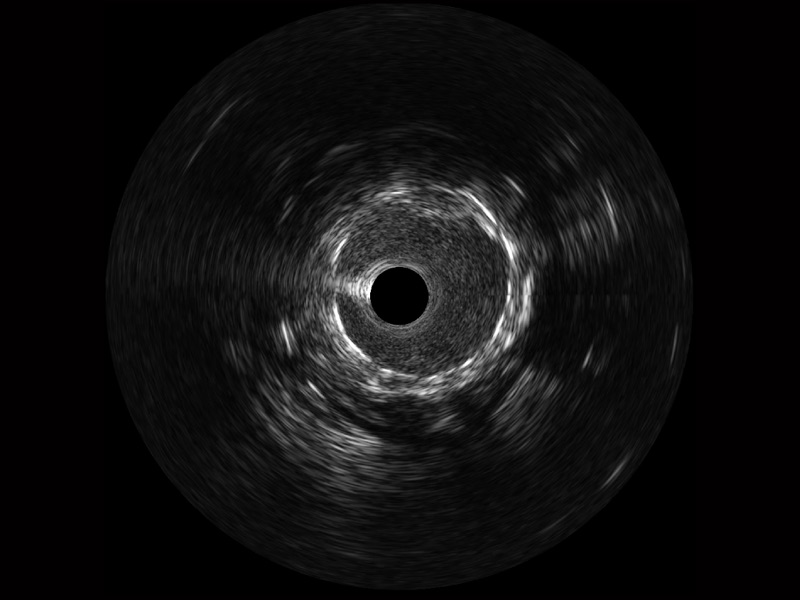

• 传统IVUS图像

对比传统IVUS导管成像,银河集团官网宽频IVUS图像的近场支架梁显影更细腻,远场中膜外血管仍清晰可辨,兼顾远中近,兼顾分辨力与穿透深度